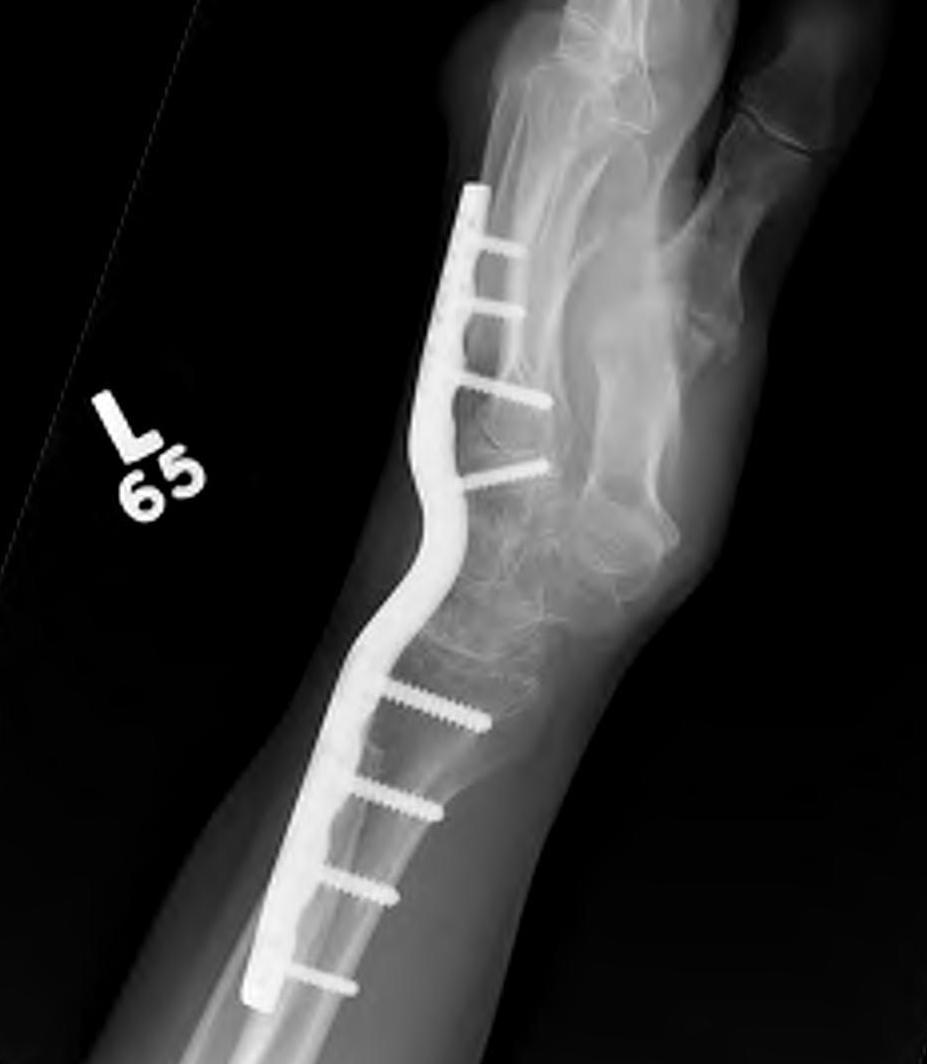

Total wrist arthrodesis

wrist fusionwrist fusion

Indications

Diffuse advance radiocarpal and mid carpal OA

Poor bone stock

Stiff wrist

Loss of wrist extensors

High demand

Technique

Wrist Fusion APWrist Fusion Lateral